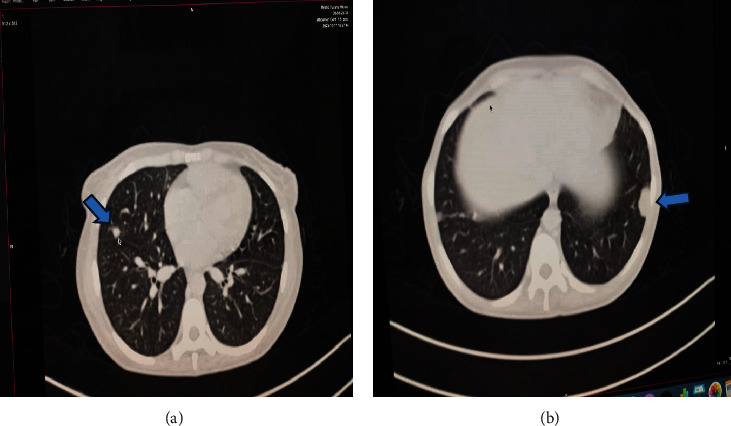

Background: Metastatic vulvar choriocarcinoma, a rare ectopic gestational trophoblastic neoplasia (GTN), often presents a diagnostic challenge due to its mimicry of other conditions, particularly in resource-limited settings. Its primary symptom is abnormal vaginal bleeding without a clear cause. Consequently, diagnosing and managing it poses difficulties for many low-resource health facilities, as evidenced by the current case. Case Presentation: We present the case of a 25-year-old, P2+2+2L2, who had a large painless, bleeding vulva mass for nearly 5 months. This followed a spontaneous abortion the month prior. The mass gradually increased in size and was accompanied by fever, pus discharge, and weight loss. Despite being treated at multiple health facilities for a vulvar abscess, there was no improvement. A diagnosis was finally made at a tertiary facility where elevated quantitative serum beta-human chorionic gonadotropin (hCG) (β-hCG) was noted. Due to uncontrollable vulva bleeding, she was referred to another tertiary facility for emergency radiotherapy. Following stabilization, chemotherapy was administered using the EMA-CO protocol. Conclusion: The report highlights the difficulty in diagnosing vulvar choriocarcinoma, underscoring the importance of a high index of suspicion. Clinical tests such as serum (β-hCG) and imaging studies are crucial for diagnosis. In resource-limited settings, a simple strip-based urine pregnancy test with serial dilutions can be sufficient for diagnosing and managing vulvar choriocarcinoma.